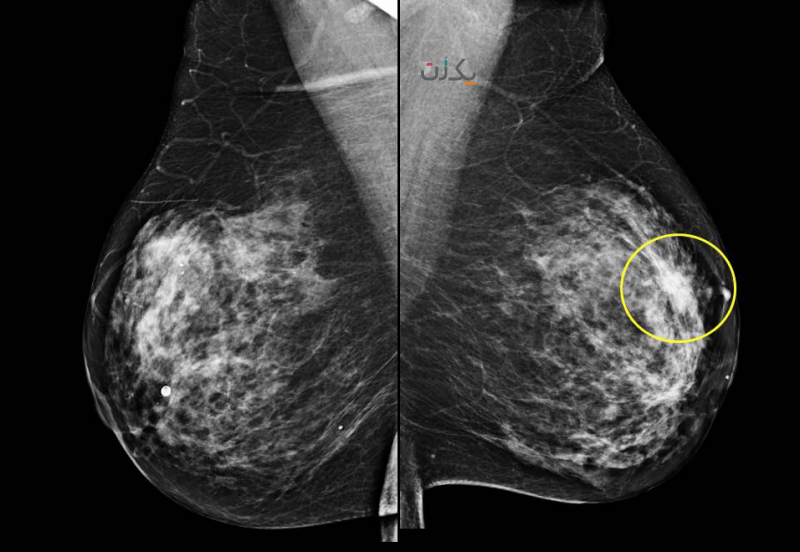

ماموگرام عکس های سیاه و سفید از بافت سینه است که ممکن است موارد زیر را داشته باشد:

- توده نواحی نامتقارن در ماموگرام

- نواحی با چگالی زیاد در بافت سینه

در ماموگرافی نقاط کلسیفیه (متراکم و ناهنجار ) به صورت نقاط سفید و چربی به رنگ خاکستری دیده می شود. این ناهنجاری ها در افراد سالمند به دلیل بافت چربی که این افراد دارند، راحت تر دیده می شوند. کیست های خوش خیم معمولا گردن و دیواره های منظم دارند اما توده های بدخیم نامنظم هستند. ولی برای اطمینان از خوش خیم یا بدخیم بودن آن باید سونوگرافی نیز انجام شود.